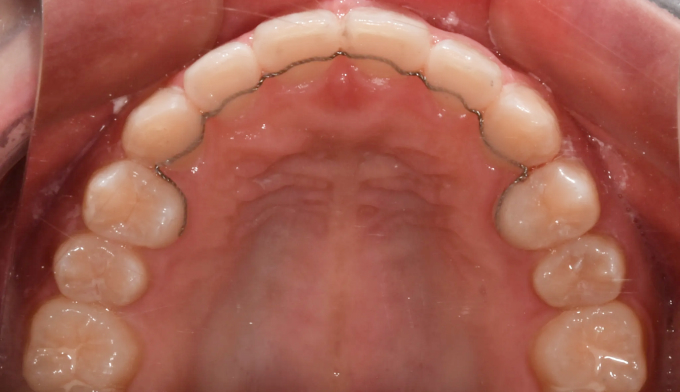

아래 앞니 하나가 선천적으로 부족한 경우이지만 주걱턱 경향으로 인해 아랫니가 윗니를 계속 자극하여 윗니까지 벌어진 케이스입니다. 윗니의 공간을 닫아주기 위하여 아래앞니를 먼저 후방이동시켜줬고, 이후에 벌어진 윗 앞니를 가지런하게 모아 마무리하였습니다. 아래앞니 하나가 부족하기때문에 위아래 가운데선을 맞추지 않고 종료하였습니다. 총 교정기간은 11개월입니다.